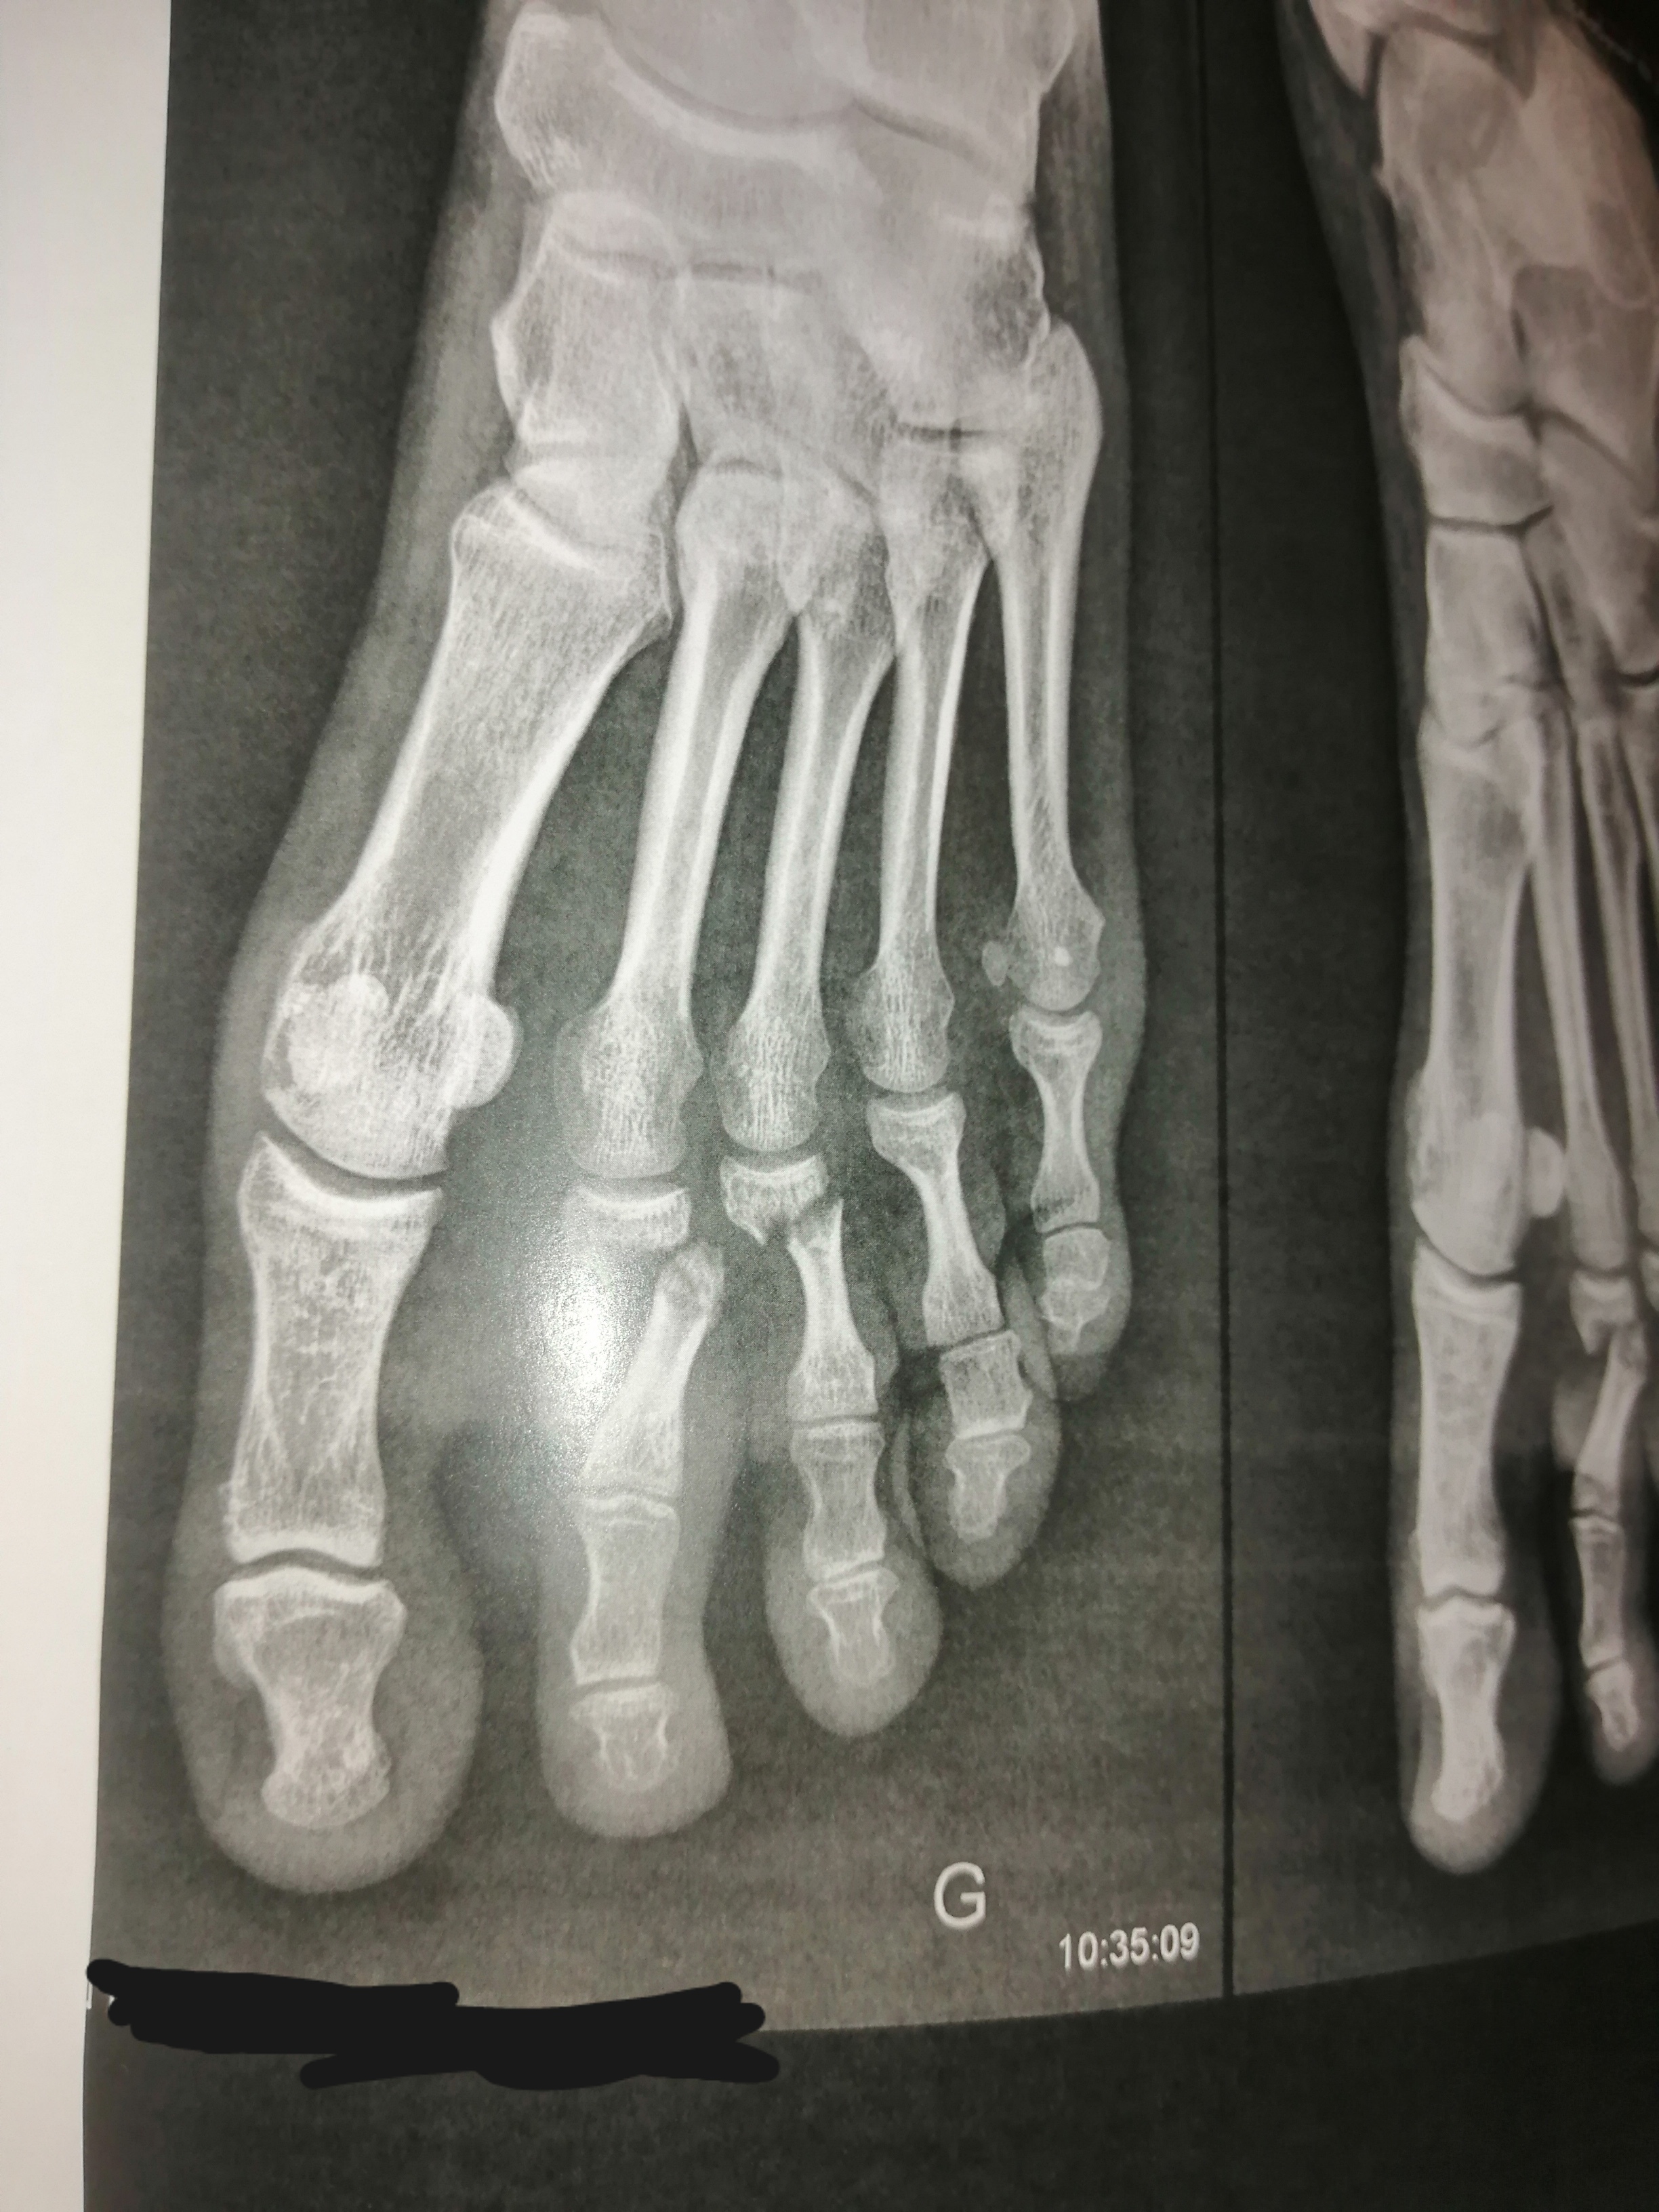

Il etait 9h mardi dernier, lorsque en rangeant des affaires dans mon futur garage, un étau en équilibre précaire (bien 15 kg) a décidé de se jetter dans le vide.

Étant d'un naturel chevaleresque, j'amorti sa chute avec mon pied gauche.

Ça pique un peu, j'enlève la chooze, la chausette et vu la gueule du pied, j'appelle les gentils pompiers.

30 minutes plus tard je suis aux urgences, radio réalisée (cliché ci-joint)

Après 4h à attendre, l'interne m'annonce que je peux rentrer chez moi !

Le chirurgien ortho peut rien faire pour le moment, c'est trop enflé.

Bref rendez vous mardi prochain pour nouvelle radio et savoir si je passe en chirurgiende suite ou pas. Depuis c'est antalgique, anti inflammatoire et canapé.